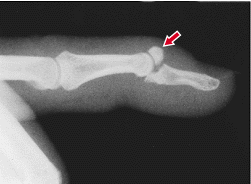

Røntgenundersøgelse mhp ossøs afsprængning.

Ved ossøs afsprængning kan lukket reposition med røntgen kontrol og efterfølgende konservativ

beh. med ovennævnte fingerskinne forsøges, - dette gælder også ved større ossøse afrivninger.